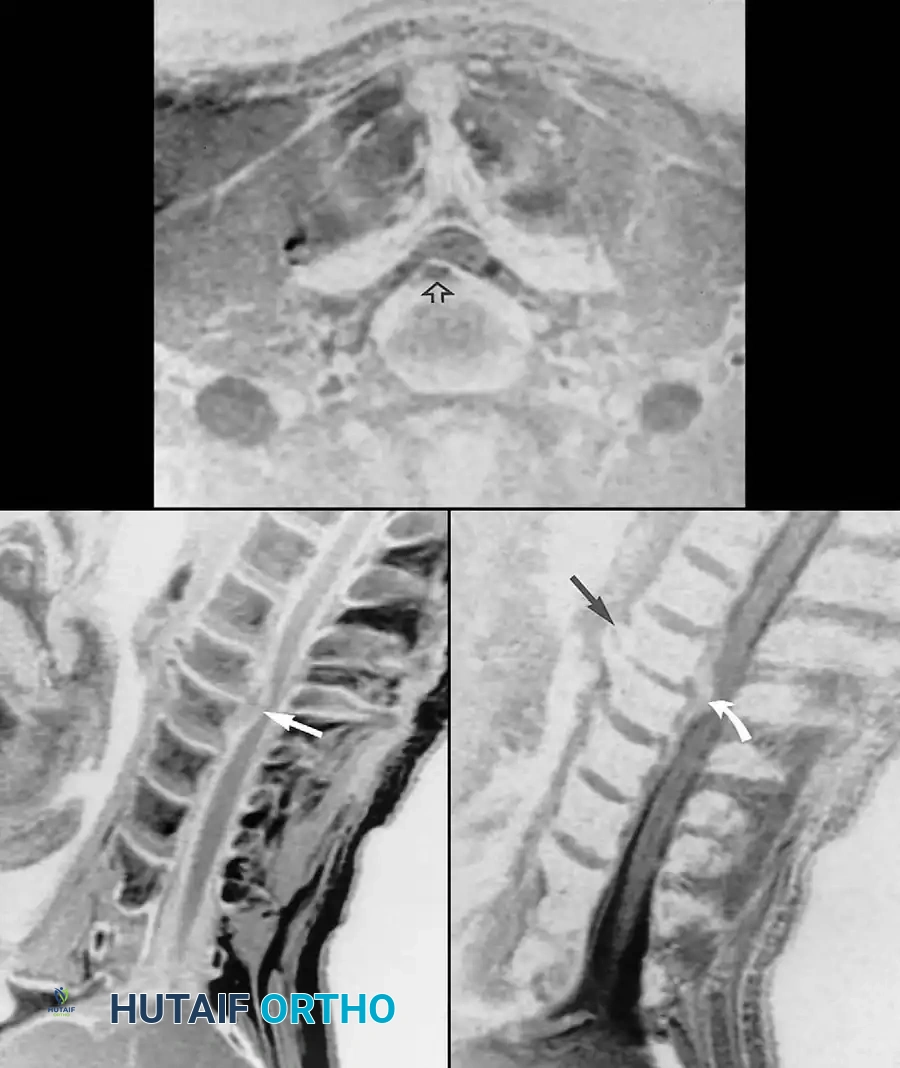

Fig. 2-25 Cervical disc extrusion (herniation). A, T1-weighted sagittal image of cervical spine reveals extruded C5-6 disc (arrow). B, Gradient-echo sagittal image produces “myelographic” effect, showing displaced disc material (black arrow) isointense to nucleus pulposus. Anterior osteophytes (white arrow) at this level are accentuated with gradient-echo technique. C, Gradient-echo axial image shows right paracentral extrusion (arrow) effacing cervical cord.

Sagittal T2-weighted or gradient-echo images create a “myelographic” effect, utilizing the hyperintense cerebrospinal fluid (CSF) to outline the neural elements, making them highly useful in evaluating compromise of the subarachnoid space. However, sagittal T1-weighted images must be examined closely to identify narrowing of the neuroforamina. The normal bright fat signal in the foramina provides excellent contrast to the darker, displaced disc material or hypertrophic facet arthropathy.

Far-lateral (extraforaminal) disc herniations are best visualized on selected axial images localized through the disc levels. Free disc fragments (sequestrations) appear discontinuous with the intervertebral disc, usually demonstrating intermediate T1-weighted signal in stark contrast to the hypointense CSF.